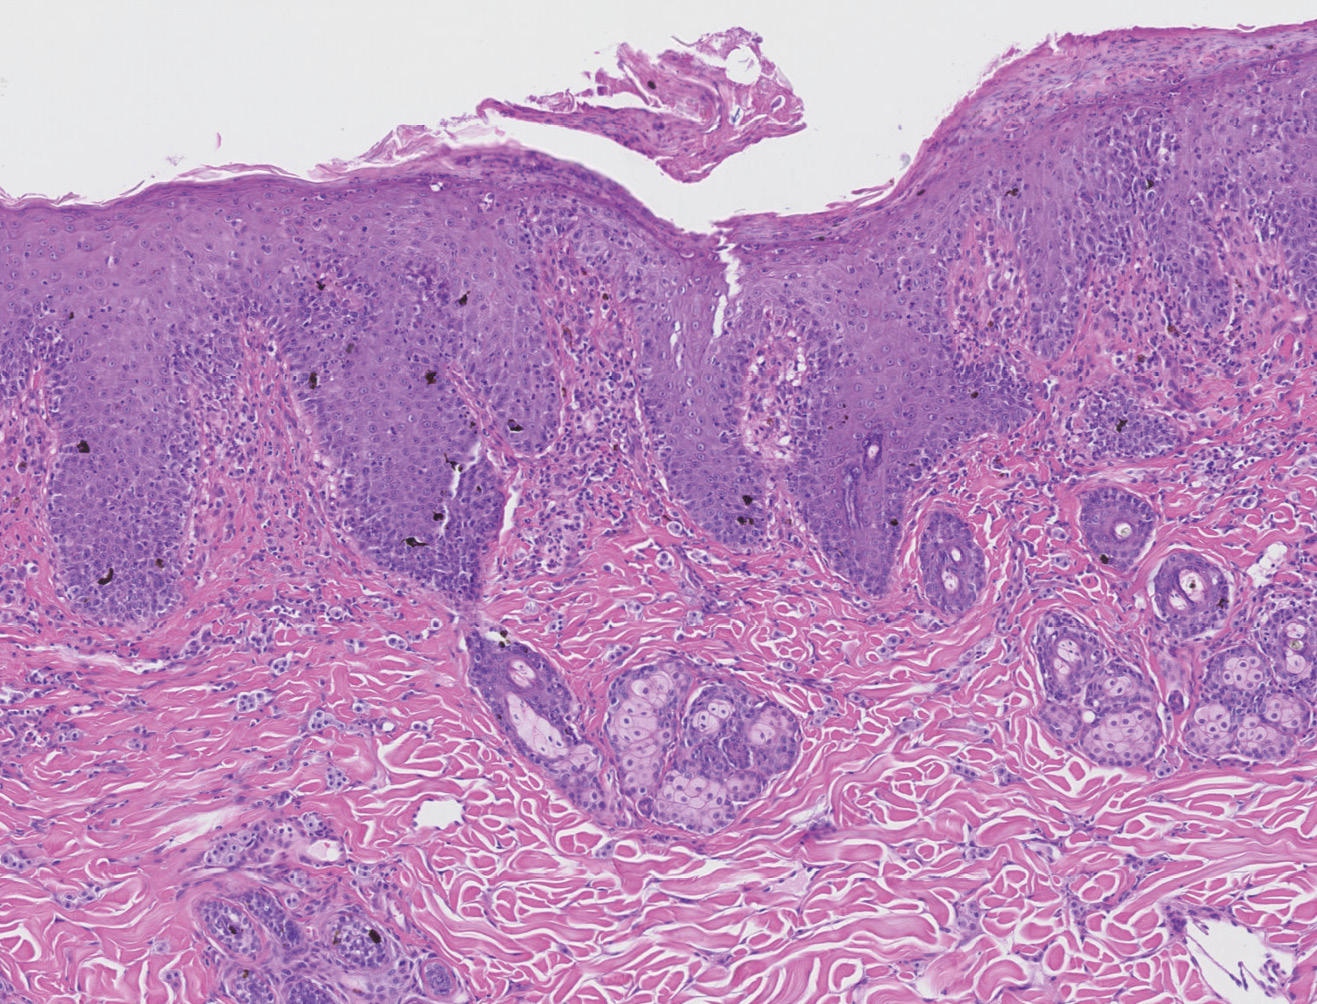

En la histopatología (imagen 2) se observa una dermatitis hiperplásica, mastocítica, neutrofílica, eosinofílica y plasmacítica, de distribución perivascular a intersticial, moderada, crónica, con formación de costras. Estos hallazgos se encuentran en los procesos de mastocitosis típicos de la raza sphynx. Según el patólogo, estos cambios también se encuentran en una dermatitis alérgica que podría ser consecuencia de atopia, alergia alimentaria, reacción a la picadura de pulgas/artrópodos o reacciones medicamentosas; por ello, el diagnóstico definitivo se obtiene teniendo en cuenta la historia y los signos clínicos.